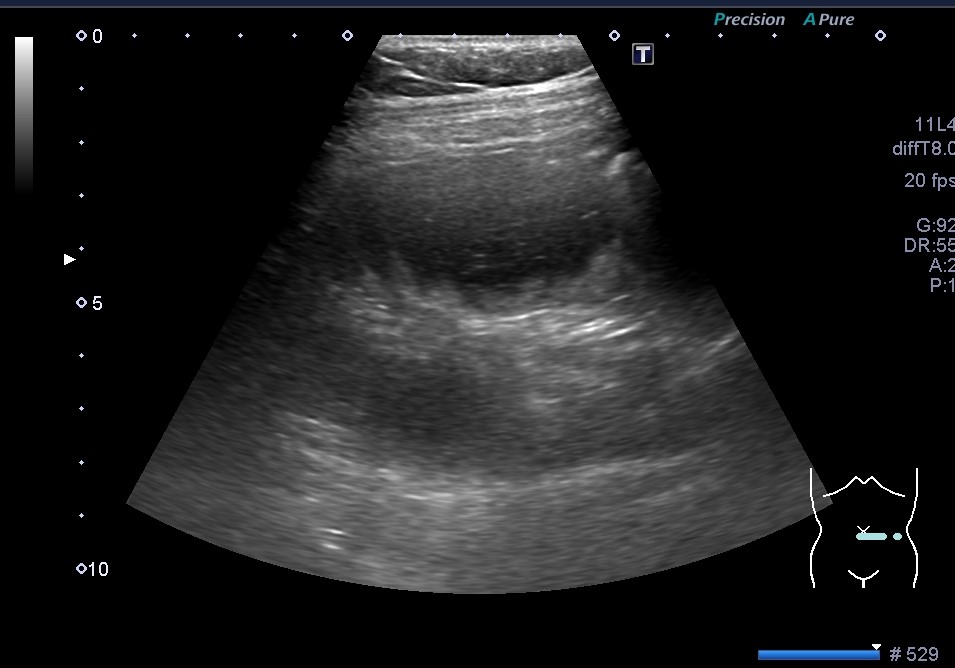

小腸イレウスと腸閉塞。エコーではパッと見、小腸が拡張している画像が得られます。

教科書にはいつも立派な小腸拡張の写真が掲載されていて、実際の検査でもプローブを当てた瞬間にわかる所見と思っていますが、ふくよかな方やガスが多い時などはやや見えにくいようです。今回は経験年数が少ない人が見落としてた所見の動画になります⇩

腸管の中のエアーは仰向けで検査すると、重力の関係で腹側にみられプローブを当ててる方向にガスがあり、後方がやや見えにくくなってきます。色んな方向からプローブを当てるとガスを避け拡張した小腸が見えてきます。

機械の性能と患者さんの体質によって教科書みたいな画像が得られず、ややぼんやり曇ったような画像になってきますね💦

「見よう!」と思わなくてもプローブを当てた瞬間にわかる腸管の拡張像も多いですが、今回は少しだけ原因を探す気持ちになって描出しないとですかね。

回盲部より約70㎝の小腸内に黒色の固形物があり、それが閉塞の原因とのことでした。